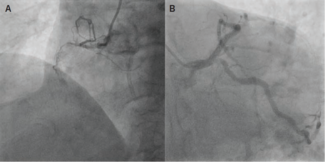

Hanif and Sheikh report a dramatic heart failure presentation caused by an acutely ruptured sinus of Valsalva aneurysm with right-atrial shunting. It was successfully treated in the cath lab with transcatheter closure using an Amplatzer Duct...